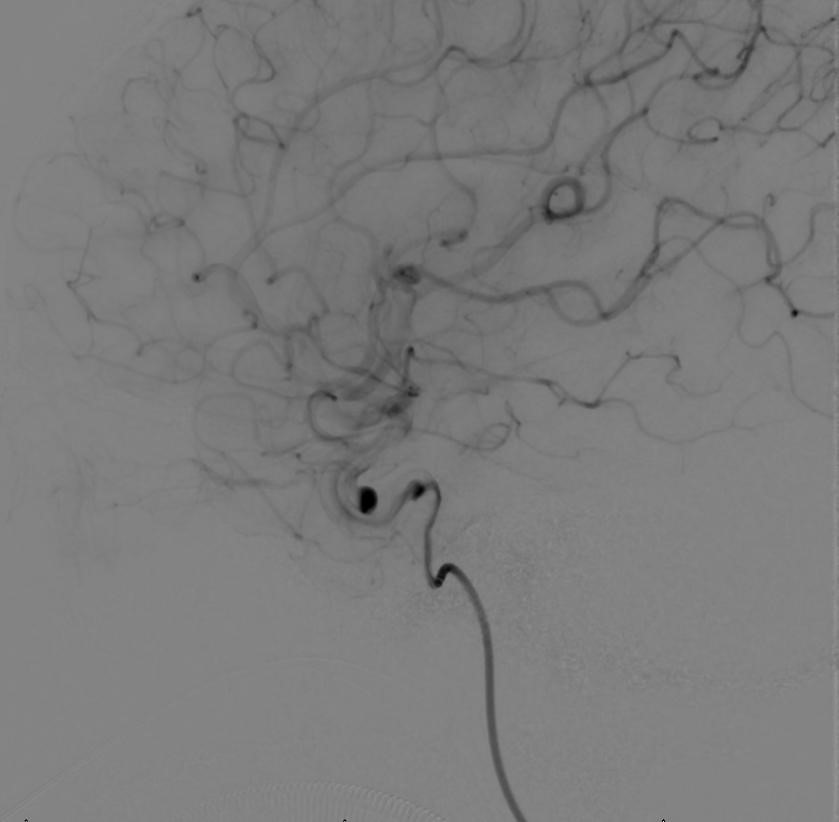

支架导管到位后,缓慢释放血流导向密网支架。

释放完全,即刻可见造影剂在动脉瘤腔内滞留